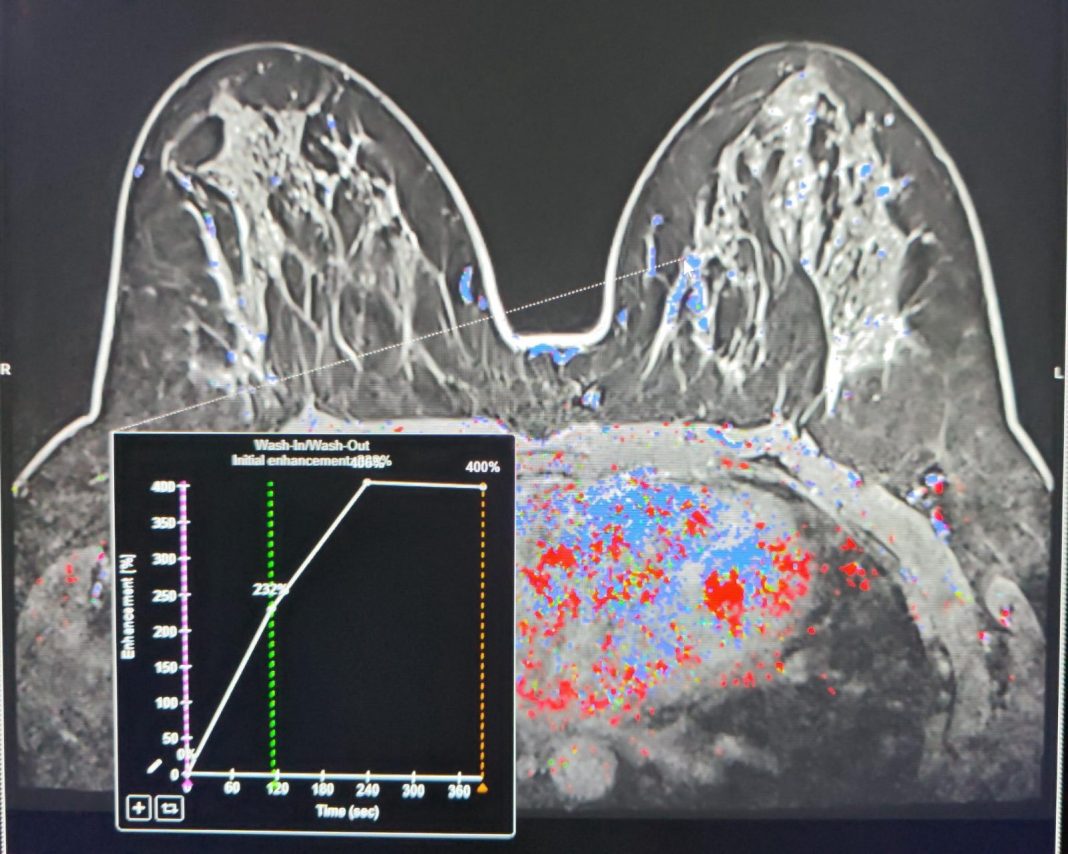

Spitalul Clinic Județean de Urgență Constanța a efectuat pentru prima dată în România o puncție mamară ecoghidată utilizând fuziunea imaginilor IRM, demonstrând eficiența noilor echipamente achiziționate printr-un proiect finanțat european.

O pacientă de 39 de ani s-a prezentat inițial la mamografie pentru o anomalie palpatorie, iar investigația a evidențiat o leziune suspectă la sânul drept. Densitatea crescută a țesutului mamar a impus completarea investigațiilor cu un examen IRM, care a identificat o a doua leziune suspectă la celălalt sân. Decizia echipei medicale a fost de a biopsia ambele formațiuni.

Prima leziune a fost abordată cu succes sub ghidaj ecografic, în timp ce cea de-a doua a necesitat corelarea imaginilor IRM cu ecografia în timp real, pentru localizare precisă și biopsiere sigură. Procedura s-a realizat cu ajutorul noului echograf de ultimă generație, achiziționat prin proiectul „Îmbunătățirea Performanțelor de Diagnostic și Tratament al Patologiilor Tumorale prin Dotarea Spitalului Clinic Județean de Urgență ‘Sfântul Apostol Andrei’ Constanța cu Echipamente de Ultimă Generație”, cofinanțat din Fondul European de Dezvoltare Regională (FEDR) prin Programul Sănătate.

“Biopsia sub ghidaj IRM rămâne standardul de aur pentru leziunile detectabile exclusiv prin această metodă, dar tehnica de fuziune imagistică oferă o soluție valoroasă în cazurile dificile și crește precizia diagnosticului”, a declarat dr. Alexandru Gavrilă, medic radiolog, specialist în mamografie.